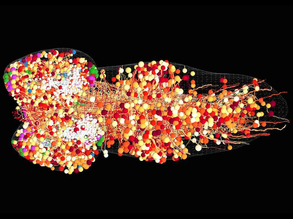

Screening for Solutions